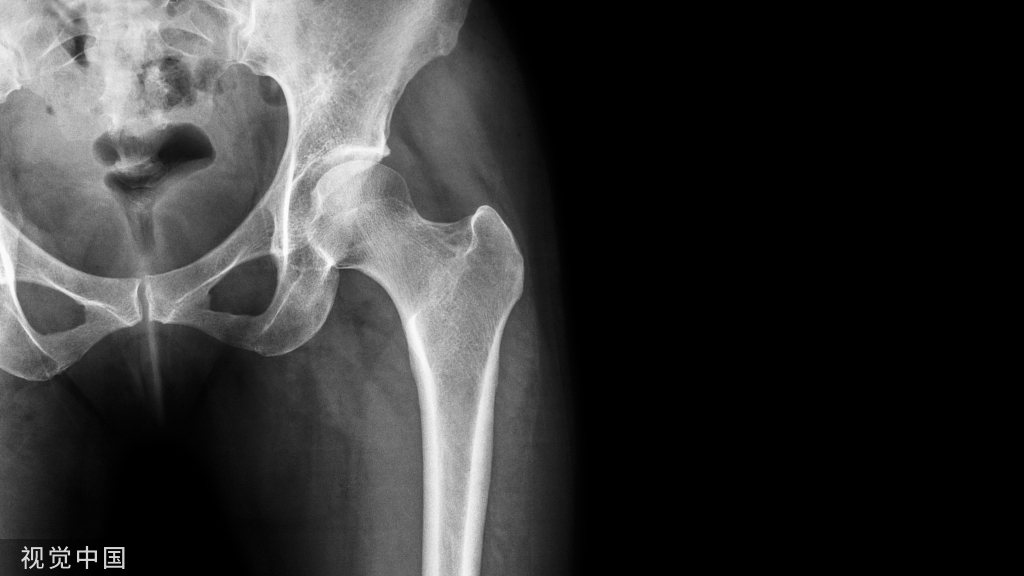

石膏固定的范围和时间:

(点击图片可放大)